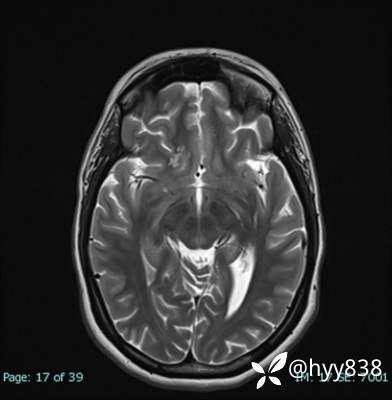

MRI sag T1WI + axi T2WI+FLAIR